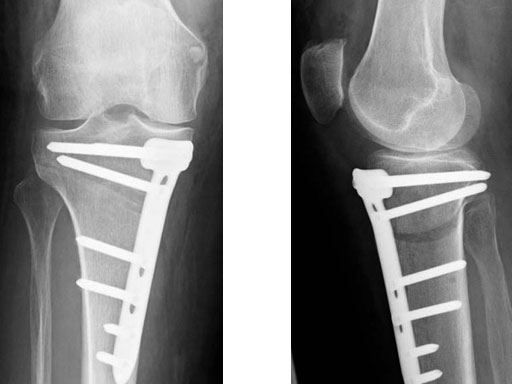

The correction is planned on a long-leg standing x-ray. After surgery, the mechanical axis should pass through a point 63% on the lateral side of the total width of the tibial plateau in the frontal plane. A transverse or slightly oblique incision is used to avoid damage to the saphenous nerve. The distal fibers of the medial collateral ligament are detached from the tibia. Under fluoroscopic control, two wires are placed in the proximal tibia marking the transverse osteotomy plane. The cut usually starts at the upper margin of the pes anserinus and ends at the tip of the fibula on the lateral side. The wires are placed exactly parallel to the tibial plateau thus taking into consideration the individual tibial slope of the patient. An incomplete cut of the posterior two-thirds of the proximal tibia is performed with an oscillating saw guided by the wires. Continuous irrigation avoids burn injury to the bone. A second osteotomy is now performed in the anterior third of the tibia in an angle of 100 ending above the patellar tendon insertion. A smaller saw blade is used and the complete anterior cortex is cut exactly in the frontal plane. The osteotomy is now gradually opened by inserting flat chisels or a spreader-chisel into the posterior osteotomy cleft. This process may take some minutes and can usually be completed without fracture of the lateral cortex. A bone spreader is now placed in the posteromedial edge of the tibia and the chisels are removed. The leg is extended and the correction is checked with the fluoroscope. A long metal rod is placed between center of the hip joint and center of the ankle joint. The projection of this rod should be at the planned point of correction on the tibial plateau lateral of the midline. Eccentric collapse of the medial joint space may cause accidental overcorrection. In this case pressure on the foot may simulate loading and body weight. The correction can be fine-tuned by opening or closing the spreader. The TomoFix Medial Tibia Plate is now placed in a subcutaneous pocket. The implant is precontoured and usually fits well to the bone surface. The distance holders avoid compression of the medial collateral ligament and the pes anserinus. Three proximal bolts are placed near the subchondral sclerosis zone. The position of the bolts is adapted to the anatomy of the proximal tibia giving optimum purchase for the bolts. An oblique lag screw is inserted distal to the osteotomy. This screw in the first combination hole allows careful compression of the lateral osteotomy hinge and pretensioning of the implant. A stab incision is created on the shaft and the implant is fixed monocortically with bolts. The lag screw and the distance holders are replaced by bolts. The medial collateral ligament is released longitudinally to reduce medial compartment pressure and the wound is closed in layers. An overflow drain may be used. Clinical and experimental work has proven that when this technique is closely followed, corrections up to and over 15 mm can be performed without bone grafting or use of bone substitutes.

The patient is mobilized on crutches on day one after surgery. Partial weight bearing is allowed from the beginning. Biomechanical and RSA studies have proven that postoperative loading of the implant by body weight in standard partial weight bearing and early full weightbearing conditions did not cause loss of correction. Our group now allows the patients to walk without crutches as soon as the postoperative pain allows after this type of surgery. Members of the Knee Expert Group (KNEG) have presently implanted over 1,500 TomoFix medial tibia. The results are extremely positive in respect to osteotomy healing, implant failure, and surgical complications.

A 68-year-old female.

Case provided by Alex Staubli, Luzern, CH